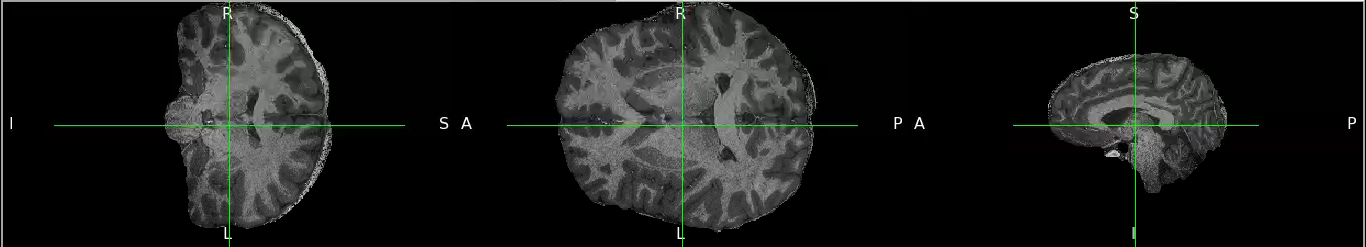

I am trying to extract the brain from T1 weighted image using antsBrainExtraction. However, the result is disappointing because part of the skull can’t be removed. I used MNI T1 weighted image 1mm as template for skull stripping and its brain mask as brain probability mask.

Do you have any kind of suggestion to improve the result ? I attach the image example.